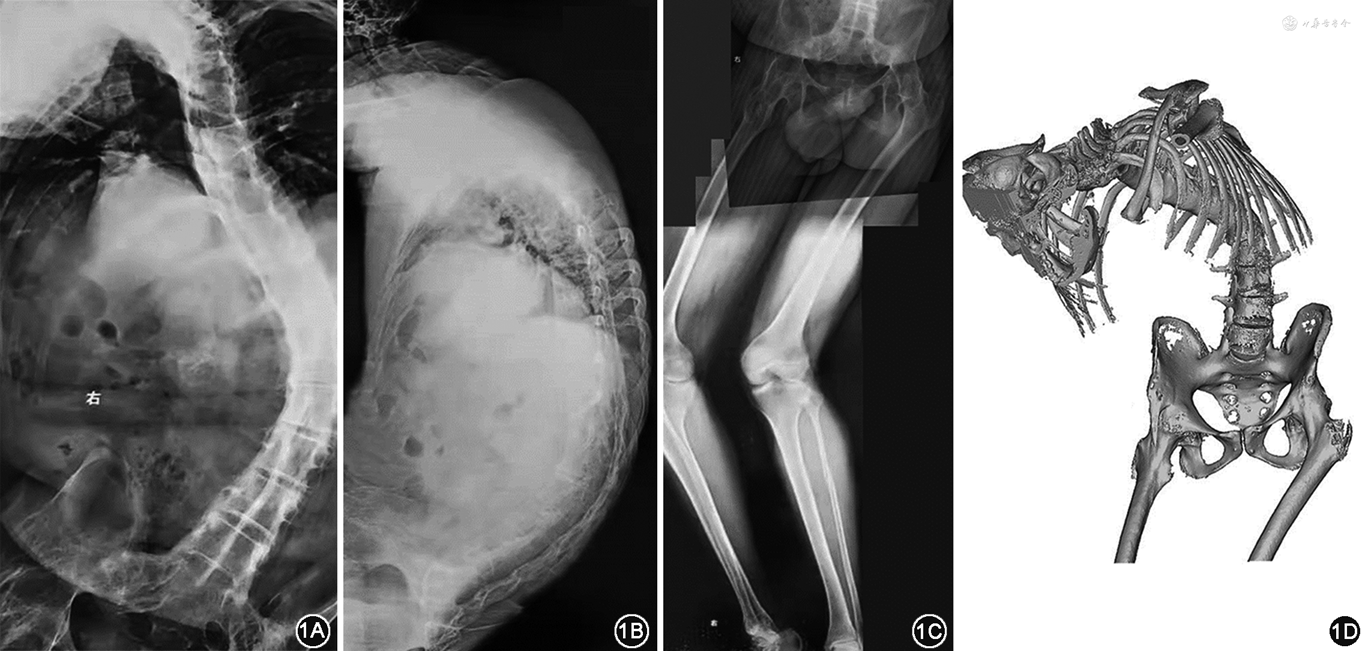

于脊柱矫形术后1、3、6、12、18个月完成连续门诊随访,观察患者整体外观、负重情况及行走能力、影像学指标、关节功能评分、并发症等指标。患者术前身高1.35 m,一期全髋关节置换术后为1.45 m,二期脊柱矫形术后为1.73 m,体重波动于60~65 kg。患者视野范围、生活质量和社会自信明显增强,罗森伯格自尊量表评分由20分升至27分。在助行器辅助下,脊柱矫形术后1周,可步行约20 m;术后1个月,增加至约50 m;术后3个月,增加至约100 m,无辅助可步行约50 m。术后5个月患者诉无法直坐,查体示髋关节屈曲活动度0°~60°,进行麻醉下手法松解后髋关节屈曲活动度0°~90°。术后6个月,可无辅助步行约200 m,可上下楼梯。术后1年,可完全负重、基本正常出行。末次随访时髋关节主动屈曲度增加至100°(图3)。髋关节功能Harris评分(术前为8分,末次随访为83分)、西大略湖和麦克马斯特大学骨关节炎指数评分(术前为230分,末次随访为83分)、健康调查简表(SF-36)评分(术前为182.8分,末次随访为572.1分)均明显改善。影像学测量数据趋于稳定(末次随访左侧髋臼外展角39.3°,右侧37.7°;左侧前倾角9.3°,右侧9.1°),脊柱功能评分显著提高(末次随访时颏眉角26.6°,脊柱侧凸研究协会22项量表评分80分,Oswestry功能障碍指数22.22%,Cobb角34.8°)。